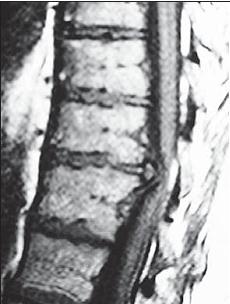

На серии снимков МРТ № 24 наблюдаются дорсальные грыжи межпозвонковых дисков в поясничном отделе позвоночника в сегментах Lv—SI Это самый уязвимый межпозвонковый диск, так как в силу своего анатомического расположения на него приходятся самые большие нагрузки. Как говорится, по счёту «последний», а по уязвимости, первый. Поэтому в нём чаще, чем в других межпозвонковых дисках, возникают, различные осложнения, в том числе и грыжи МРТ № 25